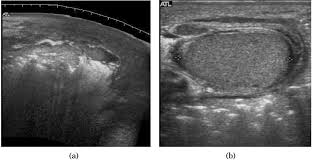

Reconstruction Of Scrotal And Perineal Defects In Fournier S Gangrene Journal Of Plastic Reconstructive Aesthetic Surgery

Reconstruction Of Scrotal And Perineal Defects In Fournier S Gangrene Journal Of Plastic Reconstructive Aesthetic Surgery from els-jbs-prod-cdn.jbs.elsevierhealth.com